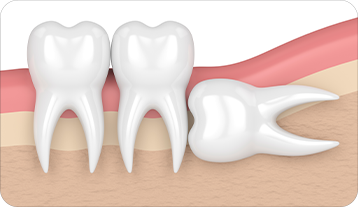

사랑니 발치란 구강 내 가장 뒤 쪽에 위치한 사랑니를

구강질환 예방 또는 해결을 위해 발치하는 것을 말합니다.

사랑니는 입안 깊숙이 위치하여 칫솔모가 잘 닿지 않아 충치와 염증이 잘 생기므로 주기적인 검진이 필요합니다.

사랑니 발치 언제 해야 될까요 ?

관리가 어려워 충치가 생긴 이유

옆으로 누워 앞쪽 치아를 미는 경우

단순발치

간단 수술 발치

복잡 수술 발치

뼛속에 있는 사랑니와

그 뼈를

절단하여 발치